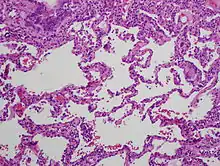

High magnification micrograph of hypersensitivity pneumonitis showing granulomatous inflammation. Trichrome stain.

Histopathology

The acute form can be characterized by poorly formed noncaseating interstitial granulomas and mononuclear cell infiltration in a peribronchial distribution with prominent giant cells.[1] The subacute, or intermittent, form produces more well-formed noncaseating granulomas, bronchiolitis with or without organizing pneumonia, and interstitial fibrosis.[1] Much like the pathogenesis of idiopathic pulmonary fibrosis (IPF), chronic HP is related to increased expression of Fas antigen and Fas ligand, leading to increased epithelial apoptosis activation in the alveoli.[21] Cholesterol clefts or asteroid bodies are present within or outside granulomas.[1]